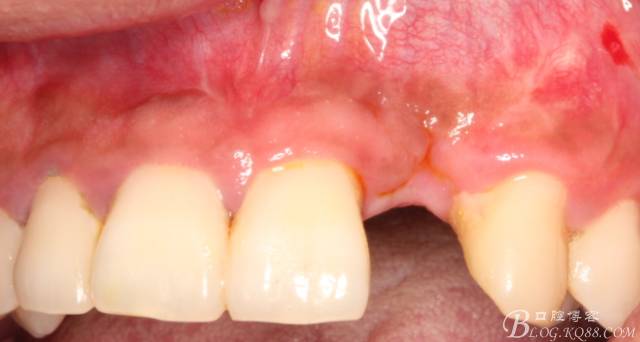

10天拆線一切正常,又過(guò)了兩周患者復(fù)診,自述期間無(wú)異常??趦?nèi)檢查,真的嚇了一跳,唇側(cè)鼓了個(gè)包,擠壓有白色分泌物溢出,絕對(duì)不是膿液,液體排除后,術(shù)區(qū)觸診空虛,外觀塌陷。這時(shí)候考研大夫的時(shí)刻到了,是先觀察一段時(shí)間再說(shuō)?還是馬上進(jìn)行處理?我的回答是:馬上處理!如果你沒(méi)有及時(shí)處理,而是放患者回家觀察,那么接下來(lái)會(huì)發(fā)生如下情況:1.回家后患者家屬及親友會(huì)有很多你可以想象得到的討論;2.患者及家屬會(huì)對(duì)你產(chǎn)生不信任,勢(shì)必會(huì)到其他門診或醫(yī)院檢查,他院大夫會(huì)不會(huì)發(fā)表對(duì)你不利的言論;3甚至?xí)蚁嚓P(guān)法律界人士找你討要說(shuō)法。

于是我果斷告知患者,手術(shù)失敗了,不能拖延,如不及時(shí)處理,炎癥繼續(xù)發(fā)展會(huì)很快波及鄰牙牙槽骨?;颊呓邮芪业慕ㄗh。切開(kāi)翻瓣,骨粉及生物膜消失了,骨吸收嚴(yán)重,幸運(yùn)的是,因?yàn)樘幚砑皶r(shí),鄰牙骨支持依然存在。